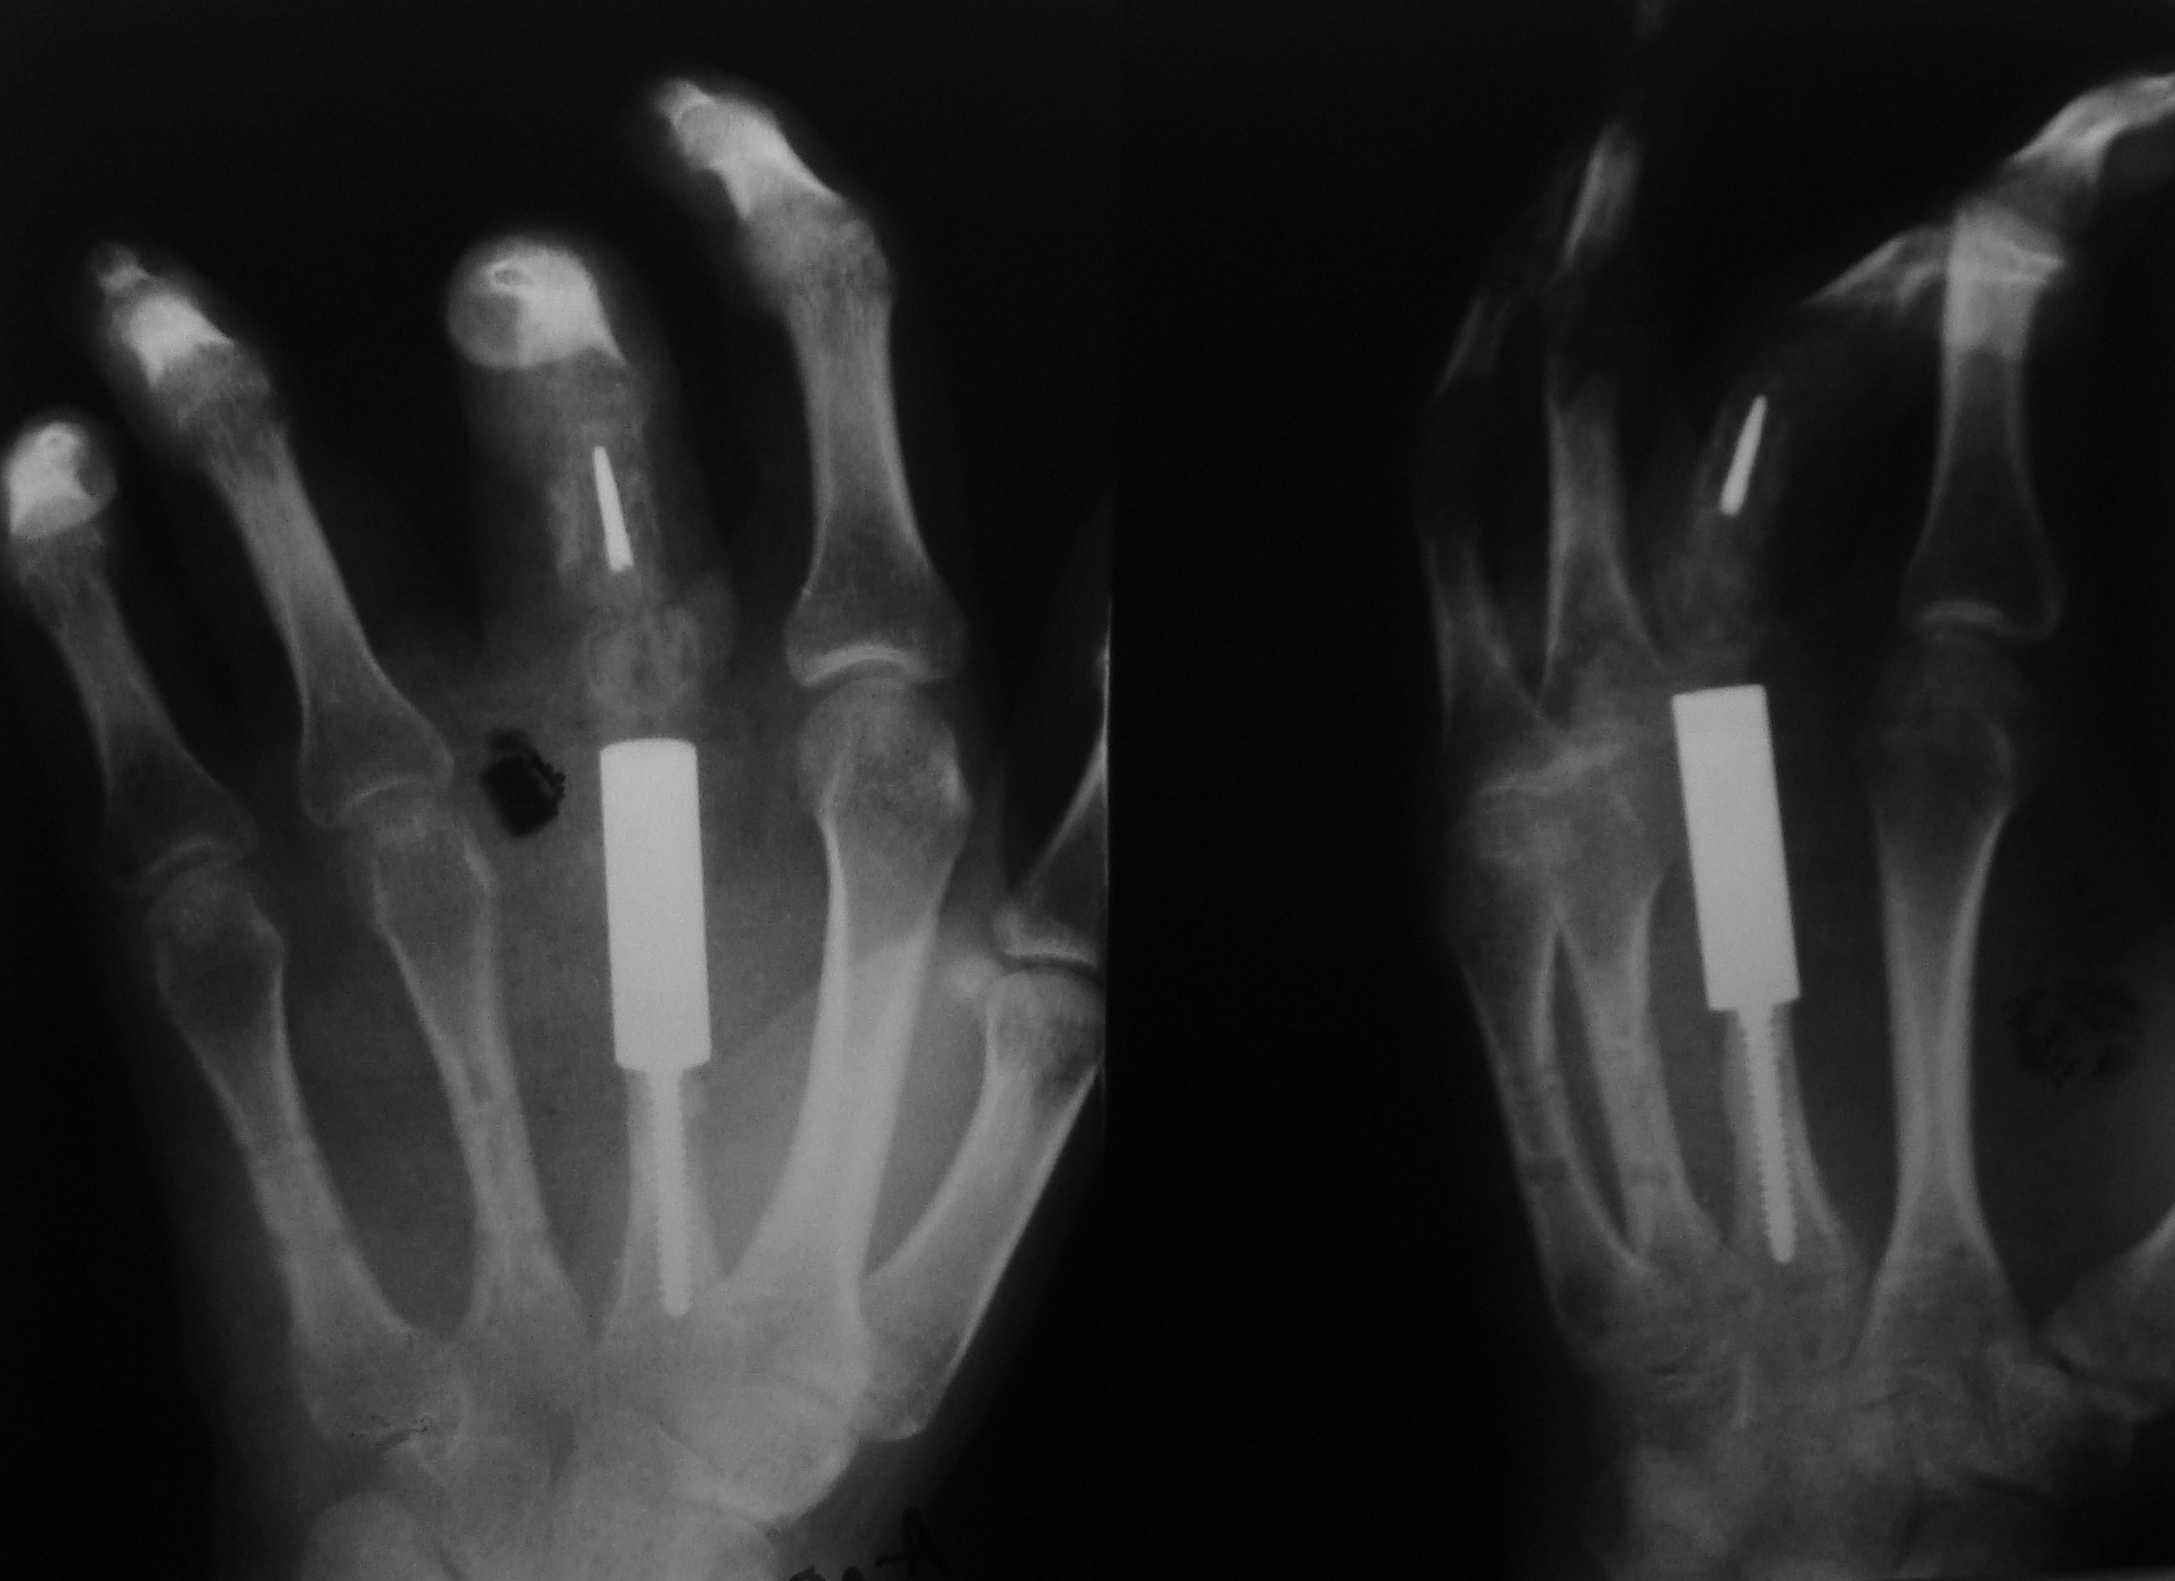

Re: ГКО 2-й пятной кости

обещанные снимки